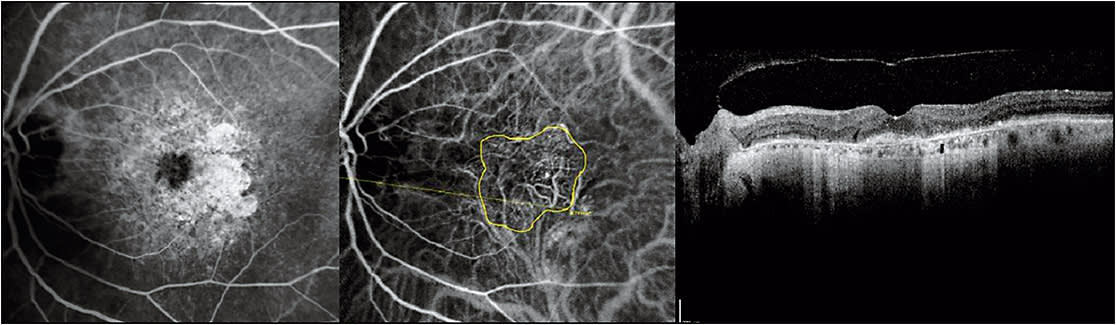

Figure 2. Fluorescein angiography (left), indocyanine green angiography (middle), and optical coherence tomography (right) of the same patient from Figure 1 after successful treatment extension to a 10-week interval. Her Snellen visual acuity remained 20/30. Notice the enlargement of the choroidal neovascularization surface area by 67.1 % ((9.68-5.79)/5.79) on indocyanine green angiography from Figure 1, but the continued absence of retinal fluid on optical coherence tomography. The subject was treated with bevacizumab and extended out to a 12-week interval.